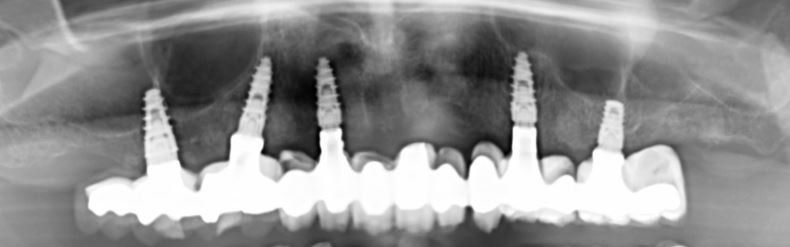

Un approccio flapless è stato usato in 11 casi e in 41 arcate è stata eseguita anche una procedura di rigenerazione (quasi nel 50% dei casi). I tessuti molli si mostravano in salute e liberi da segni o sintomi di mucosite al momento della rimozione della protesi provvisoria, così come all’ultimo follow-up nel 90% dei casi (Fig. 6). Il controllo radiologico ha dimostrato costantemente una sostanziale preservazione dell’osso marginale per l’intera coorte di pazienti (Fig. 7).

Fig. 7_Radiografia panoramica a 3 anni dall’intervento in cui si apprezza il mantenimento dei livelli ossei peri-implantari.Nuovo paragrafo